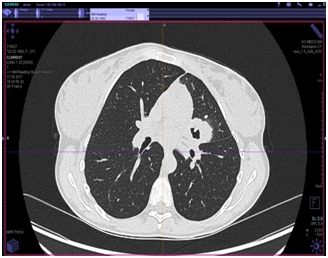

КТ органов грудной клетки (от 17.08.2017 г.)

Заключение: массивные инфильтративные изменения в верхней доле левого легкого полностью неясного генеза, возможно имеет место как воспалительный специфический характер поражения с распадом, так и осложнение пневмонии с формированием абсцесса, злокачественный процесс с распадом мало вероятен.